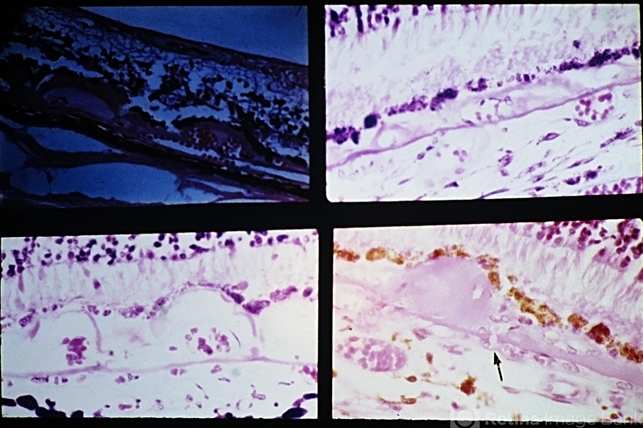

- drusen, macular, Bruch's membrane

- Vascularized drusen in periphery (upper left) and macular area (upper right and lower left). Note the tiny break in Bruch's membrane (arrow) with a choroidal vessel with an erythrocyte extending into a peripapillary druse.